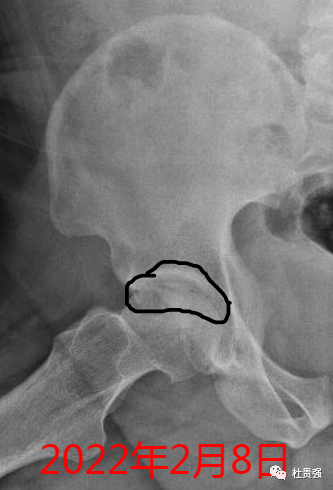

经过锻炼后见下图,新月征明显得到了改善,坚持不懈就是成功

病例二

虽然新月征仍然明显,但经过几个月随访,已经认识到围塌陷期的重要性,下一步结合功能锻炼,期待有好的临床效果。

出现新月征股骨头早期塌陷的标志,不要灰心丧气,通过努力,成功就在前方!